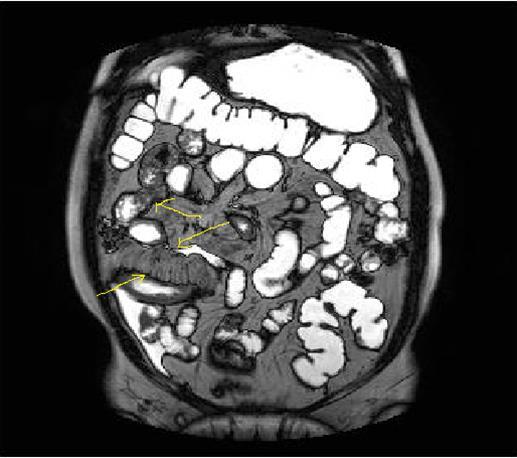

Bowel wall thickening with increased luminal and extra-luminal signal changes on FS images, showing active inflammation, edema in the adjacent intraperitoneal and mesenteric spaces, active inflammation; bowel wall thickening and enhancement on post-contrast T1W images plus high signal intensity on T2W- FS images7, 9, 12, 14, 17, 18, 19, 20, 21 (Figure 4a-b).

Chronic disease without active inflammation; Bowel wall thickening and enhancement on postgadolinium T1W images plus low signal intensity on T2W-FS images with possible stenosis and obstruction due to fibrosis, chronic disease with active inflammatoryexacerbations;these conditions can overlap with active inflammation, require longitudinal repeated scanning7, 12, 14, 20,26, 27, 28, 29, 30 (Figure 5a-b, Figure 6a-b)

Figure 4a.Mucosal involvement and lack of opacified ileal segments with loss of intestinal folds and increased bowel wall thickness due to Crohn’s disease on T2W coronal sequence after OCA, presented at 37 years old male with moderate Crohn’s disease.

Figure 4b.Mucosal, luminal and bowel wall involvement in Crohn’s disease with skipped lesions, seen at T2W axial image after OCA, presented at 45 years old male with severe inflammatory disease.